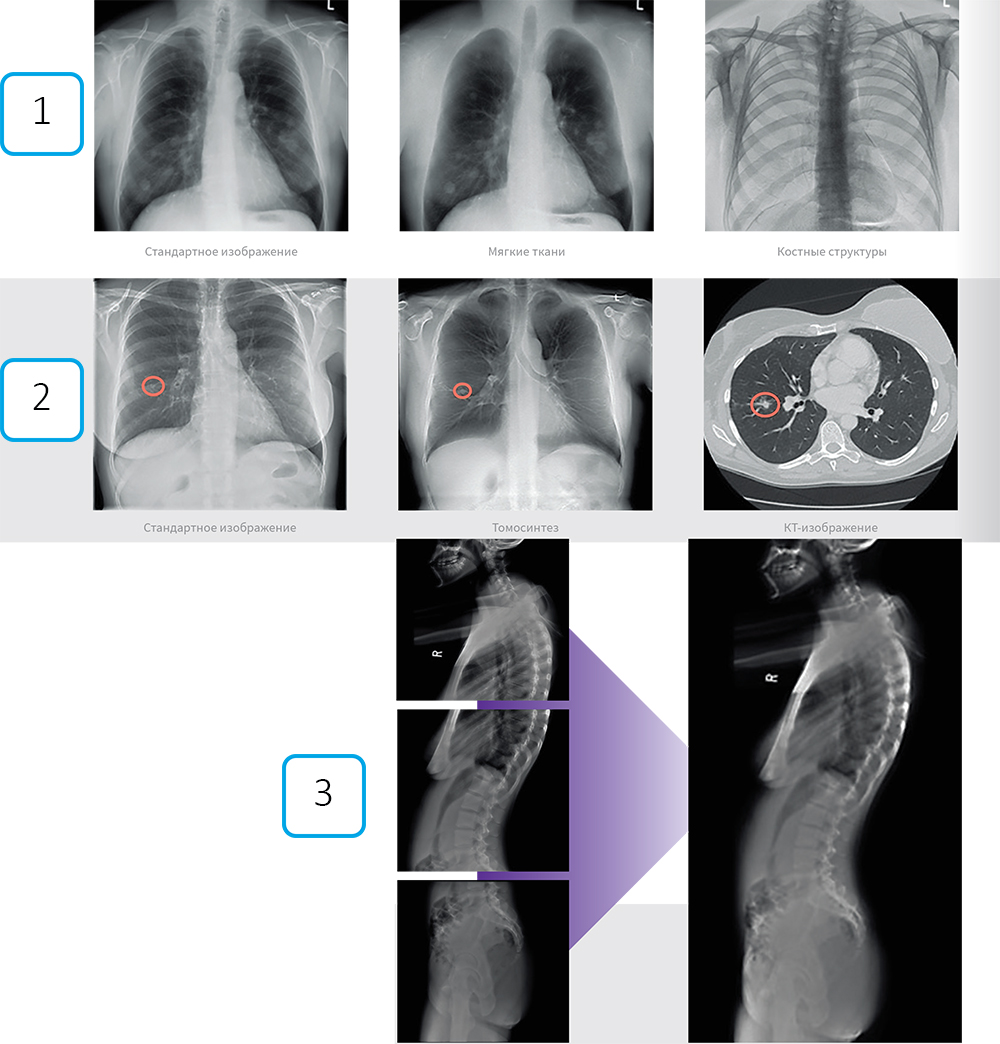

- Двухэнергетическая субтракция (ДЭР)

За один сеанс система делает два снимка с разной энергией излучения. Их компьютерная обработка позволяет получить три независимых изображения: стандартное, только мягких тканей и только костных структур. Это повышает точность диагностики патологий легких и костей без увеличения лучевой нагрузки.

- Томосинтез

Аппарат за один проход делает серию низкодозовых снимков (до 60 кадров) с разных углов. Программа создаёт из них послойные срезы исследуемой области. Технология устраняет эффект наложения органов, что особенно полезно при обследовании легких и молочных желез, снижая необходимость в дополнительных КТ-исследованиях.

- Автоматическая сшивка снимков

Для изучения протяженных зон (весь позвоночник, нижние конечности) система автоматически делает серию кадров и объединяет их в единое панорамное изображение без швов. Это обеспечивает высокую точность измерений при диагностике сколиоза или планировании операций на суставах.

- Подавление костной ткани (Bone Suppression)

Специальный алгоритм искусственно удаляет изображение костей с готового снимка грудной клетки. Это помогает лучше визуализировать затемнения в легких, которые могли быть скрыты за рёбрами, выступая дополнительным инструментом анализа без повторного облучения.